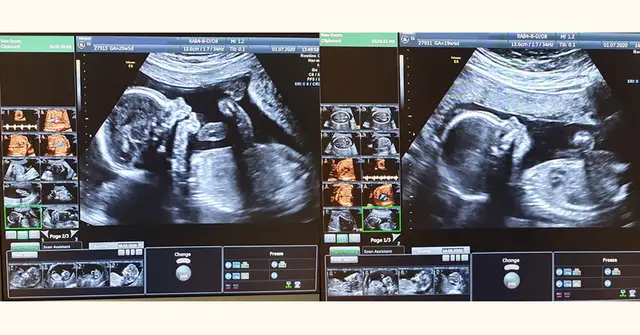

Badania prenatalne w 12 tyg. ciąży: USG genetyczne i PAPP-A bez obaw

Badania prenatalne w 12 tyg. ciąży: USG genetyczne i test PAPP-A. Poznaj cel, przebieg i interpretację wyników. Zyskaj spokój!